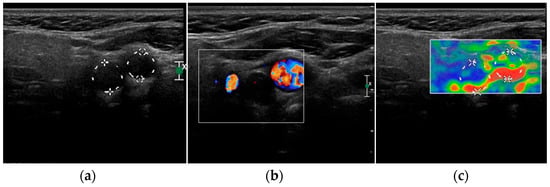

- Mohammadi, A.; Moloudi, F.; Ghasemi-rad, M. The role of colour Doppler ultrasonography in the preoperative localization of parathyroid adenomas. Endocr. J. 2012, 59, 375–382. [Google Scholar] [CrossRef]

- Vitetta, G.M.; Ravera, A.; Mensa, G.; Fuso, L.; Neri, P.; Carriero, A.; Cirillo, S. Actual role of color-doppler high-resolution neck ultrasonography in primary hyperparathyroidism: A clinical review and an observational study with a comparison of (99m)Tc-sestamibi parathyroid scintigraphy. J. Ultrasound. 2019, 22, 291–308. [Google Scholar] [CrossRef]

- Liu, H.; Liao, Q.; Wang, Y.; Hu, Y.; Zhu, Q.; Wang, L.; Liu, Q.; Li, J.; Jiang, Y. A new tool for diagnosing parathyroid lesions: Angio plus ultrasound imaging. J. Thorac. Dis. 2019, 11, 4829–4834. [Google Scholar] [CrossRef]

| Parathyroid adenoma | Enlarged, circumscribed, hypoechoic, oval shaped lesion, delineated by hyperechoic halo. Cystic inclusions may be seen. | Feeding polar vessels entering the pole and then extending around the periphery. | Early peripheral hyperenhancement. Central wash-out in the later phases. | Stiffer than hyperplastic parathyroid glands. |